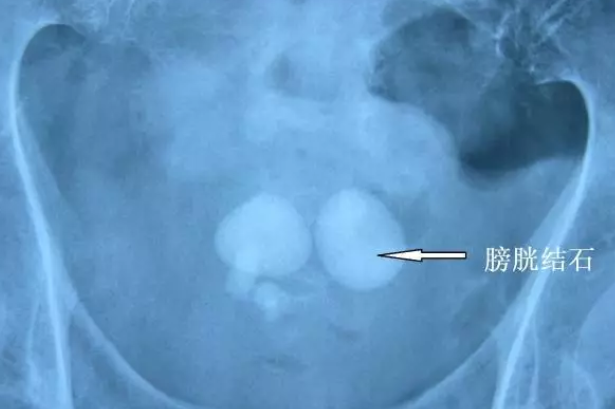

图片

异物(节育环)导致的结石